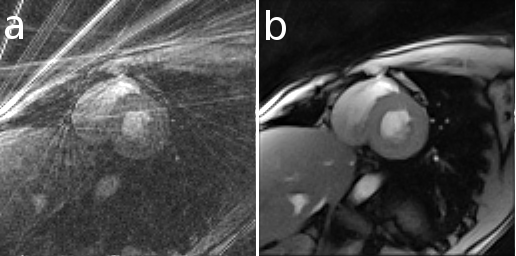

Here is an example that illustrates the benefits of iterative image reconstruction for cardiac MRI.[19]